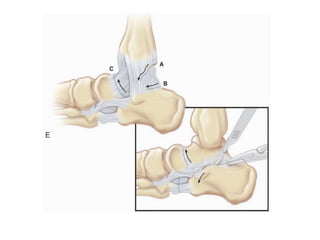

TURCOS ONE STAGE RELEASE

• First complete one-stage posteromedial release

• curved posteromedial incision

• complete subtalar release

• release of the calcaneofibular ligaments

• posterior tibialis tendon being lengthened or

released

• The Achilles tendon and long toe flexors are

lengthened and repaired

• talonavicular joint opened dorsally, medially,

and inferiorly, and the calcaneonavicular

spring ligament released

• The talonavicular joint is reduced and pinned

• Turco immobilized his patients for a total of 4

months and removed the K-wires at 6 weeks

• Night splints were used for an additional year

after the end of cast immobilization

• emphasized plantar fascial release and

capsulotomy of the calcaneocuboid joint